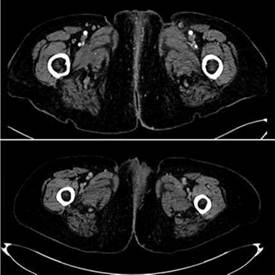

Los paraclínicos iniciales con Hb:13,8 g/dL, leucocitos 3300 mm3, plaquetas 161000 mm3, creatinina:0.6 mg/dl, Albumina 3,6 d/dL, proteínas totales 7.6 g/dL, DHL:107. La TAC inicial con engrosamiento cutáneo de los labios mayores, así como estriación de la grasa subcutánea, ganglios inguinales bilaterales menores de 10 mm. Cavidad uterina con lesión sésil de 23 mm en relación a mioma. La revisión de patología confirma enfermedad de Paget con focos de carcinoma invasor.

Se ofrece manejo local con radioterapia externa 50 Gy mas braquiterapia endocavitaria total 48 Gy. Presenta recurrencia local a los 7 meses de tratamiento siendo la misma irresecable. (fig 1) por lo que se inicia tratamiento sistémico con carboplatino AUC de 5 y paclitaxel a 175 mg/m2 . Tras 6 ciclos de tratamiento con respuesta parcial y disminución de más del 50% (figura 2B). La RNM con disminución de más del 80% de la lesión vulvar. (Fig. 2). Actualmente se encuentra en vigilancia, con mejoría clínica del dolor y la ulceración.